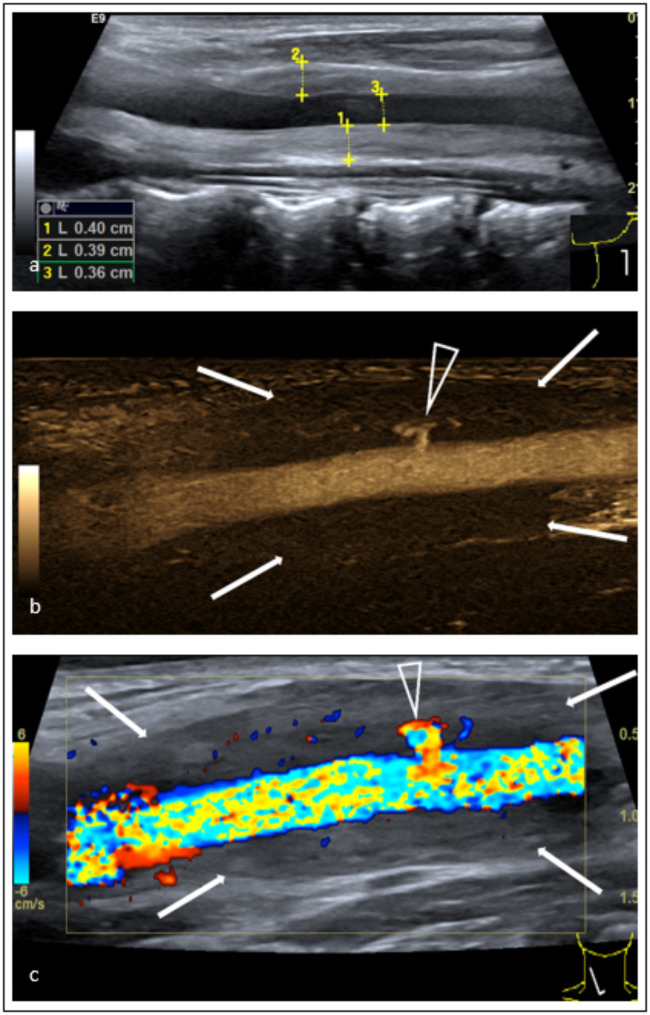

Abstract Image